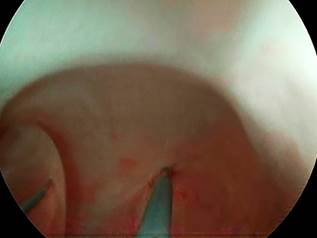

Se trata de un paciente de 32 años que presenta ingestión accidental de cáusticos, lo cual lo lleva a una neumonitis química y obstrucción completa del esófago. Después de una estancia de 2 semanas en la unidad de cuidados intensivos (UCI), se recuperó del cuadro agudo del cual salió con una gastrostomía endoscópica. El paciente fue enviado un mes después para hacer dilataciones. Cuando se hizo la primera endoscopia de dilatación, se observó una estenosis completa de la luz esofágica, por lo que se intentó recanalizar por endoscopia digestiva y por endoscopia retrógrada a través de la gastrostomía, sin éxito (Figura 1). Posteriormente, dado que no se logró la recanalización, el paciente fue llevado a una esofagectomía con anastomosis esófago-faríngea con la formación de un neoesófago. Dado que la estenosis era muy alta, el neoesófago fue anastomosado paralelo a la orofaringe. Después, la anastomosis presentó una estenosis posquirúrgica, por lo cual se hicieron unos cortes radiados de la anastomosis (Figura 2).

El paciente recurrió nuevamente al mes con estenosis, por lo cual se hizo un plan de dilataciones con dilatadores de Savary (Figura 3), pero infortunadamente, cada 10 o 15 días el paciente presentaba nuevamente estenosis. Se intentó el manejo con inyección de corticoides en los cuatro cuadrantes sin éxito, por lo que se colocó mitomicina C instilada en el sitio de la estenosis sin éxito. Por lo anterior, se decidió pasar a un plan de autodilataciones como última alternativa dado que el paciente estaba requiriendo sedación cada 8 a 10 días para hacer la endoscopia con dilatación. Primero, el paciente fue entrenado guiado por endoscopia (Figura 4) y, luego, una vez el paciente estaba entrenado, empezó a hacerse autodilataciones interdiarias con un dilatador de Savary n.° 14 (Figura 5), las cuales han sido exitosas hasta la actualidad, y ya ha completado aproximadamente 3 años.

Nuestro reporte presenta un caso exitoso de las autodilataciones para el manejo de las EEBR, y se muestran en las Figuras 1-5 y en un video en YouTube (https://youtu.be/94KkDmKgMsQ) paso a paso todas las técnicas que se usaron para resolver la estenosis compleja y, finalmente, las autodilataciones, en este caso con un dilatador n.° 14 de Savary, para que sea puesto en práctica en la comunidad médica y beneficie a pacientes seleccionados como este.